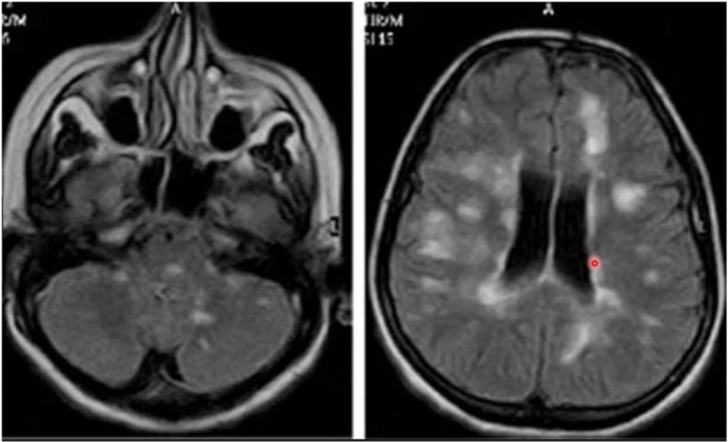

- Periodvis ostadighet, rotatorisk yrsel, synpåverkan, nedsatt hörsel, svårigheter att gå (motorik/sensorik nedsatt), inkoordinerade ögonrörelser (inflammation i ögonmuskelkärnornas (3, 4, 6) förbindelser, nystagmus

- MR-bild visar inflammationslesioner periventrikulärt och även på lillhjärna och hjärnstam (typiskt)

När kan detta ses?

Multipel skleros